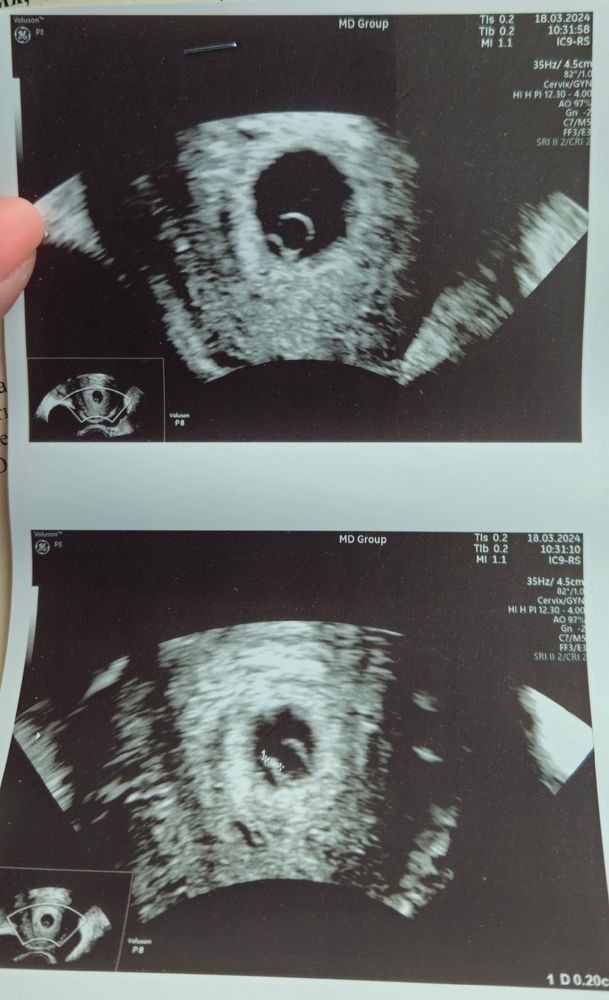

Я БЕРЕМЕННА !21 ДПП сегодня. Утром я как на крыльях летела на узи. Приехала к РЕ, муж зашел со мной, начали делать узи . Видим ПЯ - выдох, видим ЖМ- выдох, видим эмбрион - шок, видим сердцебиение - двойной шок. Хотя РЕ говорит что было ожидаемо, ХГЧ рос оч хорошо ведь, муж посмотрел на монитор, показали ему СБ и эмбрион ,единственное что он спросил - почему такой маленький? 🤣🤣🤣

Следующее узи 29.03. начинаем потихоньку убирать эстрогены.